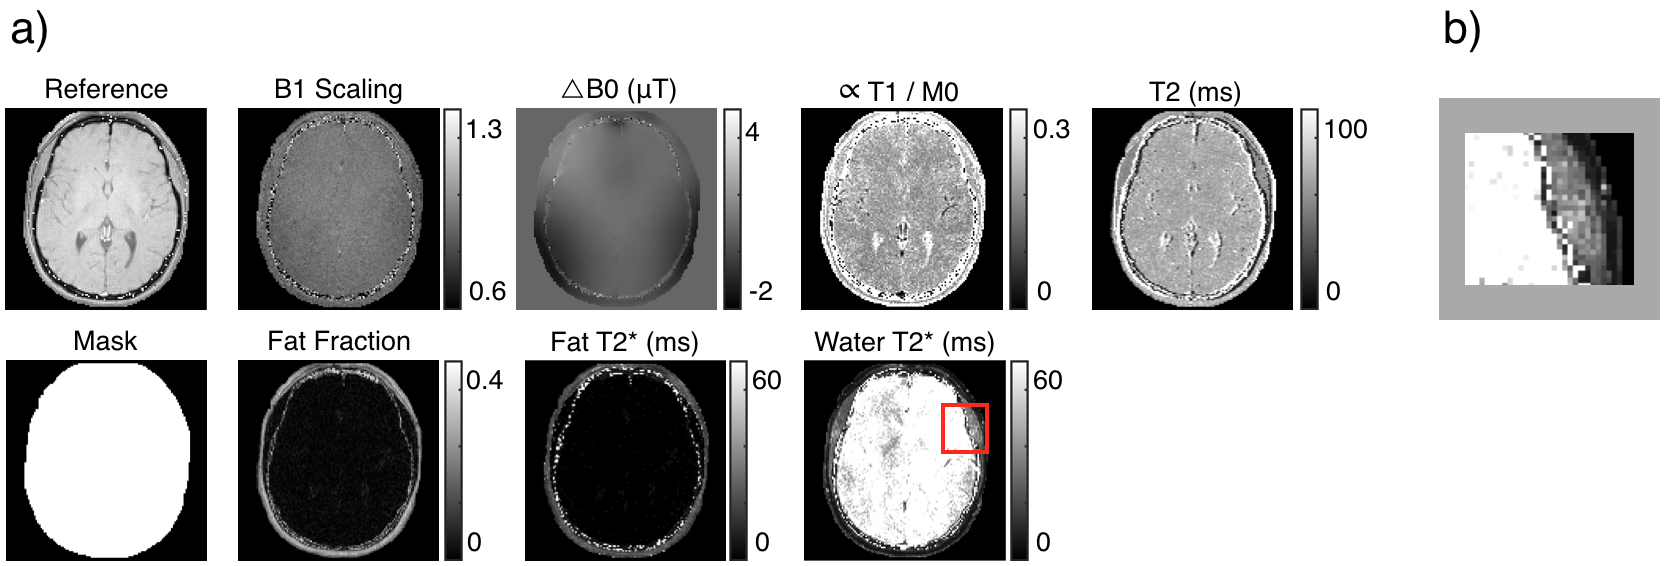

Images of an axial slice of a brain of size were collected with a kHz receiver bandwidth with a kHz receiver bandwidth and a mm slice thickness. The field of view was cm. A single-channel quadrature birdcage head coil was used for both excitation and reception.

For imaging the brain, the multiMap sequence used had a TR of ms and a of ms. The mask accurately isolates those pixels corresponding to tissue. The map accurately depicts similar proton density in brain parenchyma, and the ventricles and top of the brain stem show darker regions. The map accurately depicts higher values in the ventricles. The fat fraction map accurately identifies that the fat is largely isolated to subcutaneous tissue. The ring of speckle in the fat fraction map (pointed to by the cyan arrow) results from the low signal intensity of bone. The of water, mostly saturated, shows that this quantity is outside the estimable range by the multiMap sequence used do to the small time difference between the saturation pulse and image . To estimate larger values, one would need to either add additional images after the saturation pulse but before the first probing pulse or spread images to a longer times (this would come at a reduced fidelity of smaller estimates.